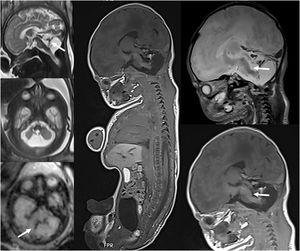

Advances in post mortem imagingPediatric post mortem (PM) imaging is an emerging technique whose use has increased as performance of invasive autopsies has decreased and the acceptance of PM imaging has increased among parents and health professionals. It includes different modalities, such as plain radiography, CT or MRI. Plain radiography continues to be the mainstay of forensic PM imaging in suspicious childhood deaths. Numerous studies have demonstrated the utility of MRI for perinatal and fetal post mortem imaging due to its capacity to visualize soft tissue anomalies, although PM CT offers advantages for identification of fractures, with a lower cost and a shorter acquisition time.4 The United Kingdom guideline for cases of suspected child abuse was updated in 2018 and now recommends performance of a PM CT scan if skeletal trauma is suspected but was not detected by plain radiography, as well as performance of PM MRI if soft-tissue trauma is suspected in the context of unexpected childhood death. Post mortem MRI is performed in fetuses or newborn infants, preferentially with whole body imaging within 24 h of birth or death (Fig. 3). Previous training in PM imaging is required to recognize normal PM findings and differentiate them from truly pathological findings. Post mortem imaging may not be diagnostic in fetuses of young gestational age.

Fetus at 33 weeks of gestational age with sonographic findings indicative of cerebellar hypoplasia. (A) Fetal MRI performed at 33 weeks showing a destructive cerebellar lesion with blood remnants (arrows). (B) Post mortem fetal MRI conducted after the pregnancy was terminated showing the cerebellar hemorrhage associated with a tegmental lesion of the medulla oblongata (arrows) that was previously undetected.